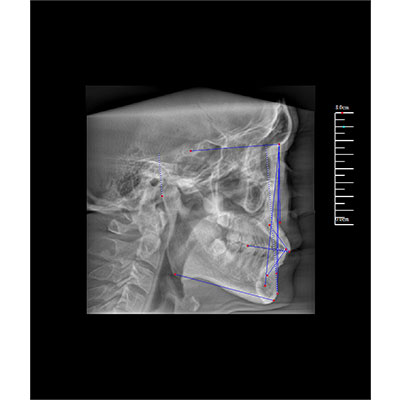

該款牙科CBCT產(chǎn)品采用動態(tài)平板探測器,獲得三維圖像的同時(shí)還具有數(shù)字化全景功能,廣泛應(yīng)用于口腔頜面外科、正畸科、正頜外科、種植科、牙體科、顳下頜關(guān)節(jié)科等術(shù)前術(shù)后。

專有三維重建算法,可提供任意位置高清斷層影像。

可同時(shí)觀察軸向面、冠狀面和矢狀面圖像,方便臨床診斷。